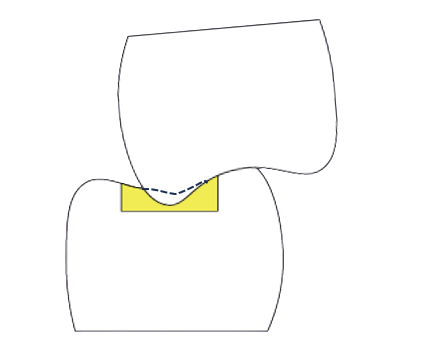

通常歯同士は接触して並んでいます。歯ぎしりや食いしばりが強いと、歯がこすれてマイクロクラックという小さな亀裂が歯にできます。 この亀裂ができると細菌が中に入り込み、歯ブラシしてもとれないため歯と歯の接触点から虫歯ができてしまいます。

日々の食事や歯軋りなどでCRに力がかかることでCRにヒビが入ったり、すり減ることがあります。

CRがすり減ることで、できた窪みに反対の噛み合わせの歯が移動してきます。

この部分で強い食い込みが起きることで、噛む時の前後左右の顎の動きによって歯が揺さぶられることになります。それにより歯の周りの骨が吸収して歯周病が進行したり、知覚過敏が起きやすくなります。

また奥歯の複数の歯にCRを繰り返し詰めることで全体の噛み合わせが低くなってしまいます。

こうした噛み合わせのバランスの悪化は顎関節症なども引き起こすことがあります。